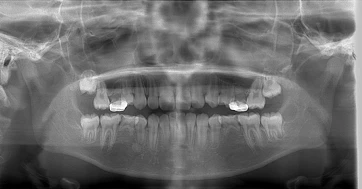

永久歯の「先天性欠如」って?

レントゲン検査で確認され、小学生の中学年〜高学年頃に発見されることが多くなります。

先天欠如によって起こる2つの問題

歯の数が合わず、歯並びや咬み合わせに影響する

上下で歯の本数が合わないと、かみ合わせや歯並びのバランスが崩れやすくなります。

大人になってから、乳歯が抜けてすき間が残る

欠如部には永久歯がないため、将来的に「すきっ歯」になるリスクがあります。